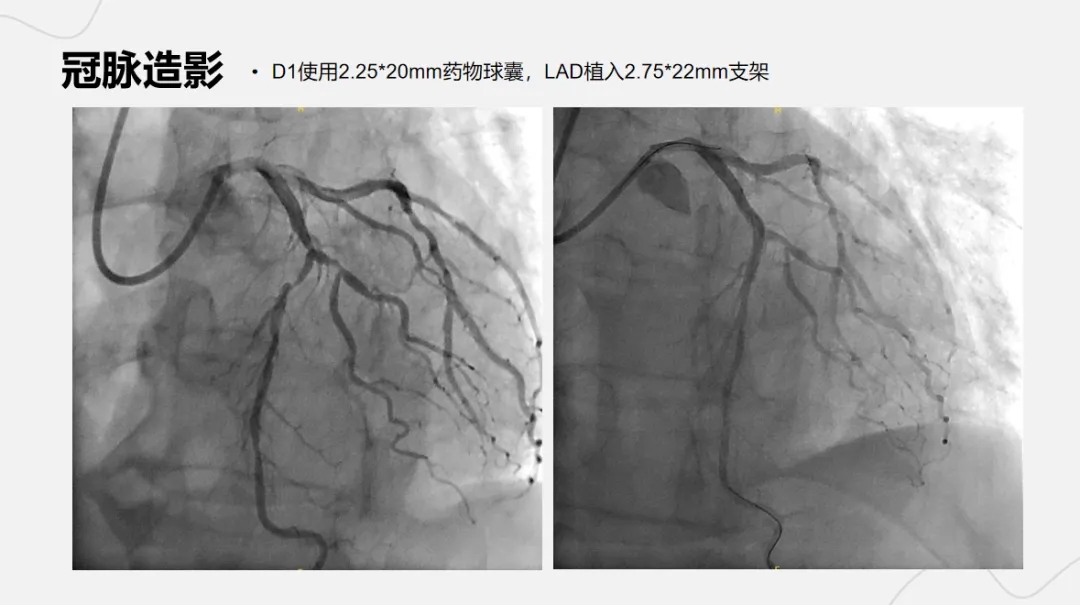

病例名称:诡异的非ST段抬高型心肌梗死